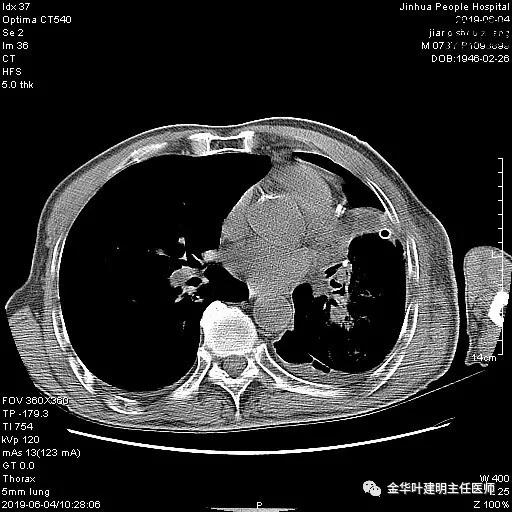

6.4上午:24小时引流出血性乳糜液1800毫升。是否再次手术进行右进胸胸导管结扎,抑或继续保守治疗非常纠结!压力非常大!!多方讨论会诊无法取得一致意见,但一般认为,引流量在1000毫升以上宜积极手术。情况与浙二医院范军强教授联系,请求指导,范教授认为左侧肺手术,损伤胸导管主干的机会较小,多数可保守治疗而愈。在他们的病例中,也有结扎胸导管后引流量仍无减少,效果并不能完全保证。建议可以考虑胸管夹管观察(因为淋巴管压力低,予以适当的压力,漏出量可能会明显减少),同时继续禁食,并静脉营养支持,引流管口可能会有渗液,注意更换敷料。与家属充分沟通后决定试夹管;这天血色素9.0 g/L;胸部CT复查示: